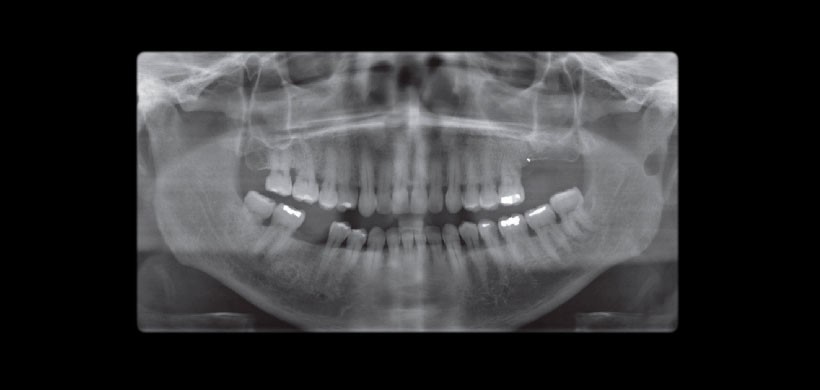

Fig 1. Radiografía panorámica muestra la depresión cortical bien en la rama ascendente izquierda.